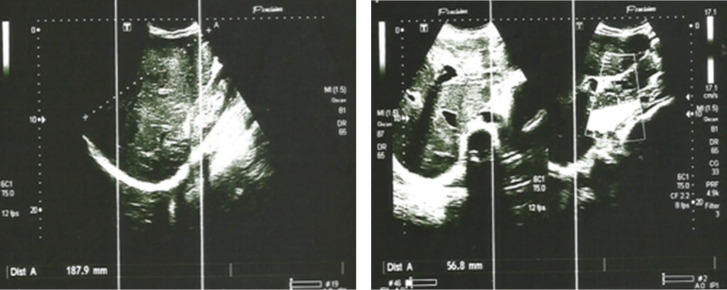

肉样瘤病是一种病因不明的多系统炎症性疾病。孤立的肺外病变非常罕见。我们报告了一例 29 岁女性患者的肝脾肉样肿大病。该患者无明显病史,因反复鼻衄就诊。临床检查发现肝脏结节性肿大,伴有门脉高压和脾脏肿大。血沉、碱性磷酸酶、血清血管紧张素转换酶和转氨酶均偏高。脾脏和肝脏活检组织学检查发现有肉芽肿性炎性浸润,但无癌症病变或扁桃体结石。主要的挑战仍然是与其他肉芽肿病的鉴别诊断。皮质类固醇疗法是一线治疗方法,脾脏切除术后,患者的临床和生物学状态均趋于稳定。

Sarcoidosis is a multisystem inflammatory disease of unknown etiology. The isolated extrapulmonary form is rare. We report the case of hepatosplenic sarcoidosis in a 29-year-old female patient.It is a patient with no notable medical history, who was seen in consultation for repeated epistaxis. Clinical examination noted nodular hepatomegaly associated with signs of portal hypertension and splenomegaly. Sedimentation rate, alkaline phosphatase, serum angiotensin converting enzyme, aminotransferases were high. Histological examination of the spleen and liver biopsy noted granulomatous inflammatory infiltration without cancerous lesion or tonsil stones.This picture is comparable with sarcoidosis, despite the absence of PET scans. The main challenge remains the differential diagnosis with other granulomatoses. Corticosteroid therapy is the first-line treatment, and after splenectomy the patient has achieved clinical and biological stability.